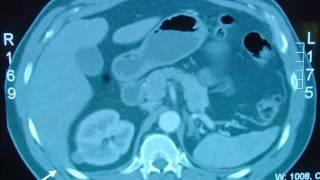

Outpatient Percutaneous Cryoablation

Outpatient Percutaneous Cryoablation

Johns Hopkins Urology